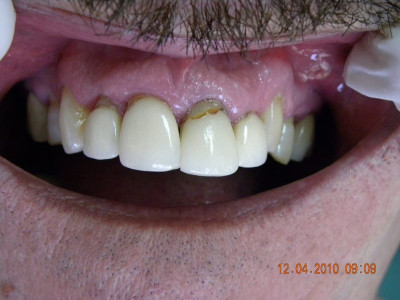

Inicio de tratamiento